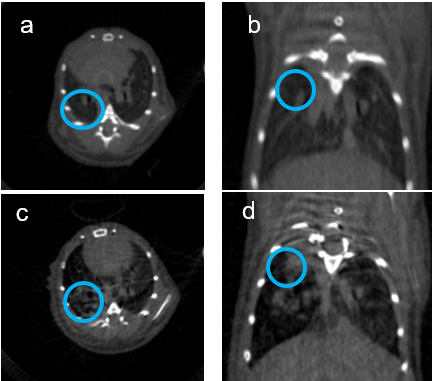

Fig. 9: In-vivo microcomputer tomography (µCT) of mouse lung. (a,b) show the mouse lung prior tumor cell inoculation and (c,d) the same mouse lung two weeks post intratracheal injection of Lewis Lung Carcioma cells. Scan options: X-ray voltage: 50 KV, X-ray current: 200 µA, filter: Al 0.5 mm, image pixel size: 84.8 µm, tomographic rotation: 180°, rotation step: 1.000°, frame averaging: 7, scan duration: 4min38s. Pictures provided by Kati Turkowski and Yanina Knepper, Department IV.